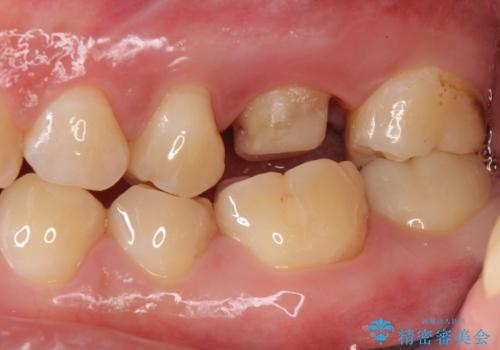

不適合な被せ物 ジルコニアクラウンでの再治療

- 検査の結果被せ物の不適合が見つかった患者様です。

ご妊娠中で安定期に治療を終わらせたいとのご希望があったため、大掛かりな外科処置は避けた治療方針で進めていきます。

被せ物を除去し、根管治療を進めた後に新しい被せ物を装着していきます。